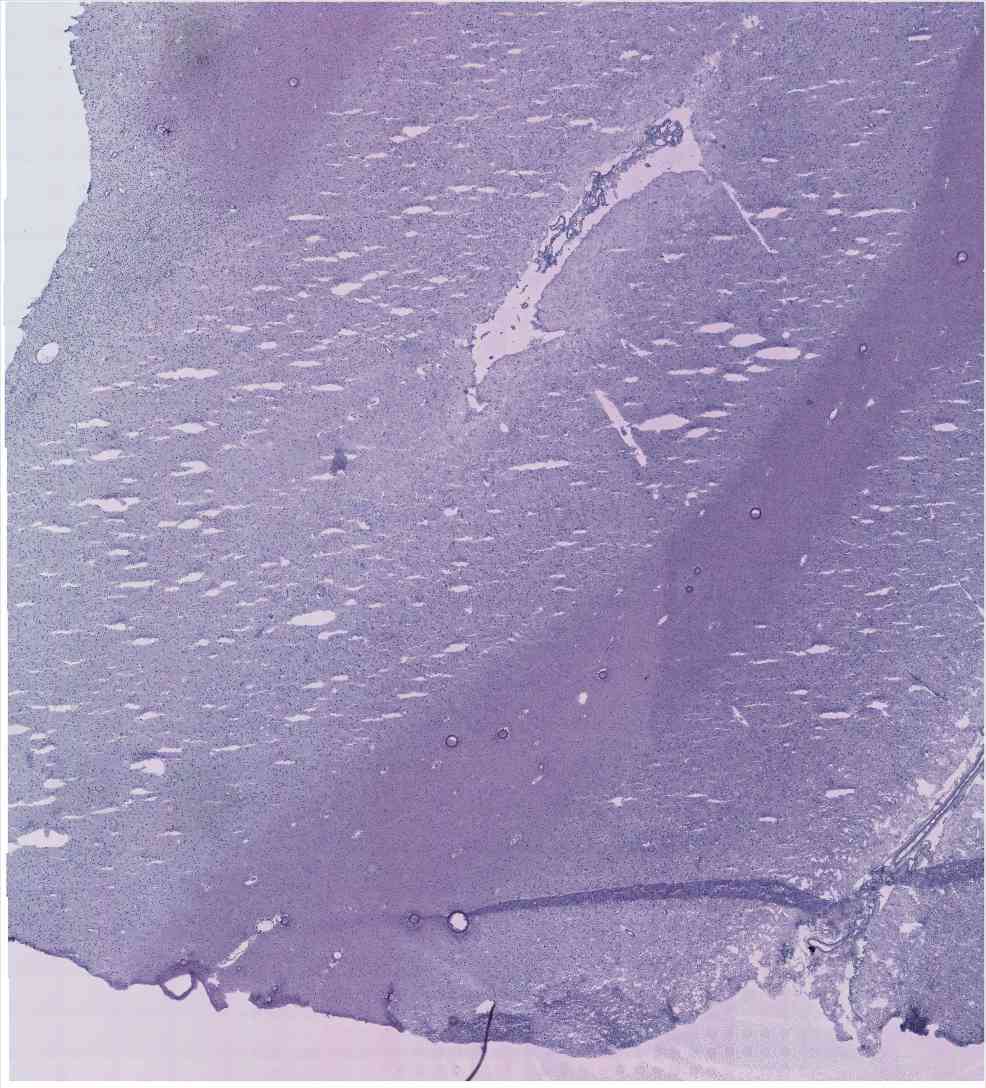

Chip 067 Well E1